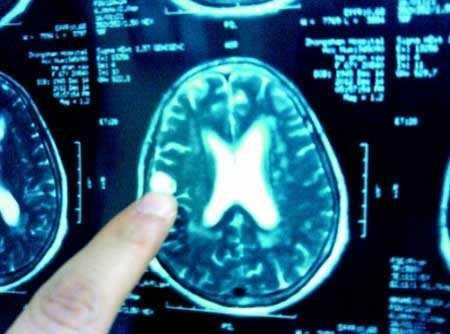

Bệnh nhân mổ thức tỉnh sẽ được bác sĩ nói chuyện, yêu cầu cử động tay, chân, hát...

Bệnh nhân mổ thức tỉnh sẽ được bác sĩ nói chuyện, yêu cầu cử động tay, chân, hát... Ảnh: Người Lao Động. |